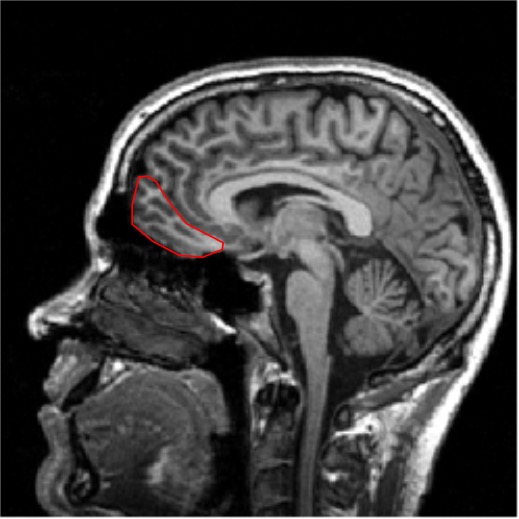

Cortical projections of gustatory pathway

From the VPM projections reach the gustatory cortex: anterior insular cortex and frontal operculum.

Information derived from different areas of the tongue is spatially segregated in the n. of the solitary tract, the thalamus, and the cortex. (Still true?)

Gustatory cortex

- Primary somatosensorycortex (Postcentral gyrus)

- Gustatory Cortex (frontal operculum andanterior insular cortex)

- Fronto-parietal operculum

- Lateral sulcus

- Insular cortex

- fig origin unknown.

Note that the gustatory cortex is very close to the tongue area on the somatosensory cortex!